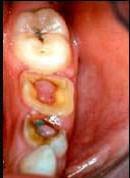

问题 临床上牙髓息肉一般见于 ( )

选项 A.慢性溃疡性牙髓炎 B.急性牙髓炎浆液期 C.急性牙髓炎化脓期 D.慢性闭锁性牙髓炎 E.慢性增生性牙髓炎

答案 E